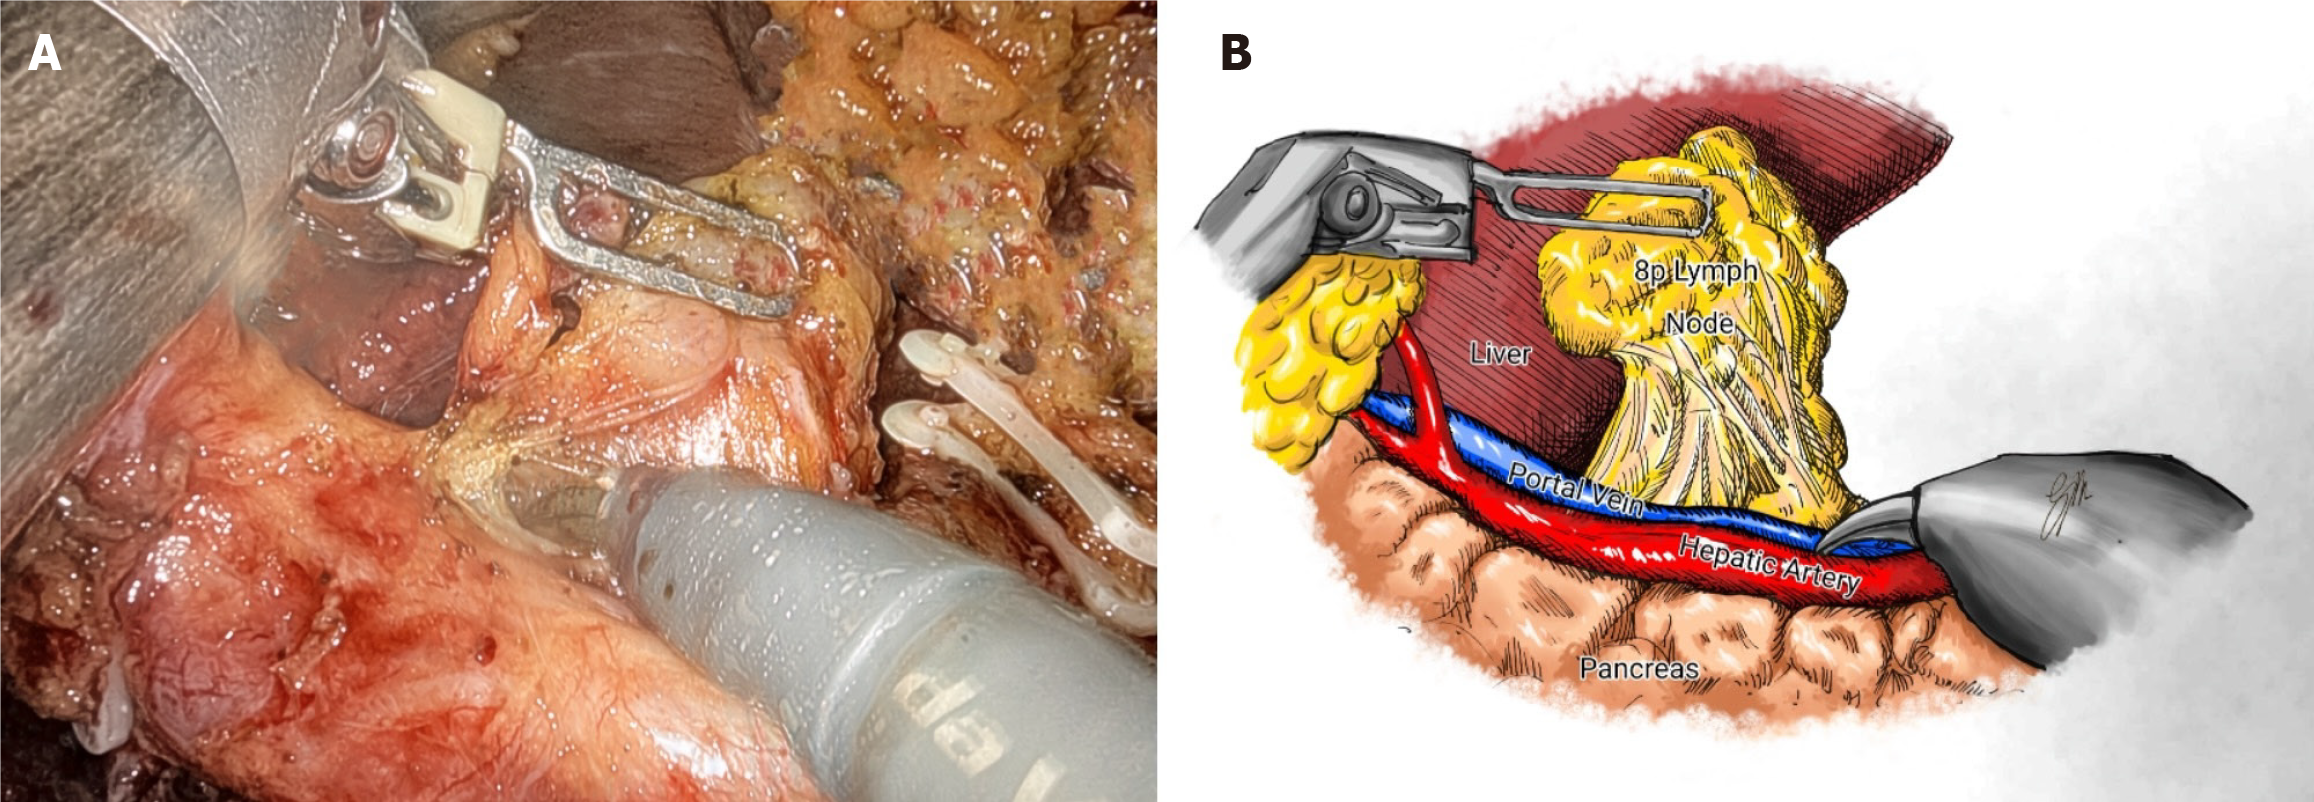

Previous reports have shown improved 3-year survival with robotic gastrectomy in patients with stage I/II GC[46]. It is generally accepted that the robotic approach can provide accurate lymphadenectomy, allowing better staging of the disease[47,48]. A recent update of the Italian Research Group for Gastric Cancer database shows a strong correlation between removed and positive lymph nodes, with this relationship reaching a plateau when 40-50 lymph nodes are examined. It suggests that survival for patients with the same number of metastatic nodes is significantly influenced by the total number of nodes removed: 12% for less than 10 nodes, 26% for 11 to 15 nodes, and 60% for more than 25 nodes[31]. As the number of lymph nodes harvested can be a predictor of survival, more extensive lymphadenectomy (i.e., removal of para-aortic and/or posterior nodes) may be indicated in GC with a high risk of extraperigastric metastases, such as located in the upper third of the stomach, with serosa involvement or exhibiting bulky nodes in the second level perigastric nodal stations[10]. No statistical differences in morbidity, mortality rates and mean hospital stay were observed compared to D2 lymphadenectomy[49]. The robotic system allows to mimic open surgical principles to perform more extended lymphadenectomy, including para-aortic nodes. In a Chinese RCT (283 patients in one high-volume hospital), more extraperigastric lymph nodes were retrieved in the robotic assisted distal gastrectomy group (RADG) (17.6 ± 5.8) than LADG (15.8 ± 6.6), particularly in the para-aortic stations (Figure 1). The noncompliance rate, defined as the absence of nodes from more than one station that should have been excised, was lower (7.7% vs 16.9%)[50]. Interestingly, the RADG group showed less intense inflammatory responses and fewer postoperative complications (9.2% vs 17.6%), resulting in faster postoperative recovery and earlier initiation of adjuvant chemotherapy.

A known problem with MIS is pancreatic fistula caused by blunt trauma from compressing the pancreas and thermal injury from continuous use of energy devices[51]. A higher incidence of pancreatic fistula was described for laparoscopic approach when compared with robotic assisted (22.5% vs 10%)[52]. Assuming that this is probably related to the higher rate of pancreatic injury during lymph node dissection at stations 6, 8a, 9, 12, and 13, the highly articulated instruments and the possibility of retroversion facilitate the access to these stations better than the retraction of the human first assistant can guarantee (Figure 2)[53]. Similarly, a Japanese trial (236 patients in two institutions) reported fewer overall (8.8% vs 19.7%) and major (5.3% vs 16.2%) complications with the robotic approach, with no cases of pancreatic fistula and a similar rate of intra-abdominal infectious complications[54].